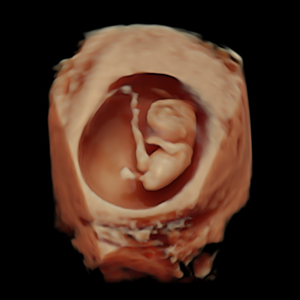

- Pionero en México en ofrecer diagnóstico por ultrasonido dentro del consultorio, así como en incorporar tecnología 3D y Doppler.